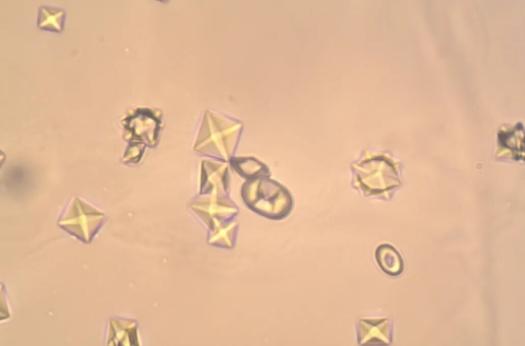

泌尿系统结石根据结石的矿物质成分又分为好几种类型。据明尼苏达大学兽医学院收集的数据,统计显示:50%左右的尿结石是鸟粪石(磷酸铵镁),33%为草酸钙,8%为尿酸盐。

而结石形成一般的过程:晶核形成——结晶生长——结晶聚集——结晶滞留——结石形成这五个部分。